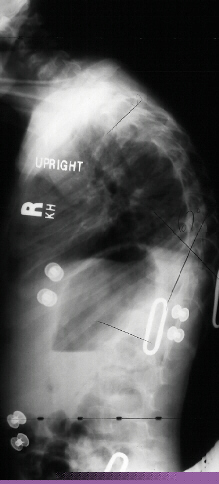

This 7 year old male presented to the cerebral palsy clinic with mild development delay, hyperactivity, and kyphosis. On physical examination he was slightly small for age (5th percentile weight for age, 10th percentile height for age) and had hyperactivity. He had no clonus or spasticity but a slightly clumsy gait. An MRI and plain x-rays were ordered (image 1, 2 & 3). After two years of brace wear the kyphosis increased to 78 degrees(image 4). The child is complaining of the brace and starting to refuse brace wear.